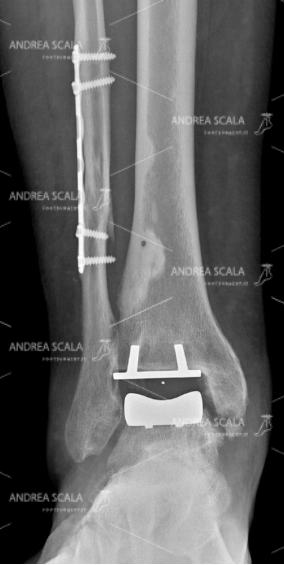

La RXgrafia anteriore della caviglia mostra la protesi della caviglia. 5 anni dopo la frattura, all’età di 39 anni, la paziente ha rifiutato l’artrodesi, cioè il blocco della caviglia e si è sottoposta all’intervento di protesi di caviglia. Si vede molto bene che la placca e le viti sul perone sono rimaste al loro posto indisturbate. Il perone non è stato toccato perché è un elemento anatomico che garantisce la stabilità della caviglia. Le componenti appaiono ben allineate all’asse della gamba.

La RXgrafia laterale della caviglia mostra la protesi della caviglia. Per quale motivo si sarebbe dovuto rompere nuovamente il perone? Perché avrebbe dovuto sacrificare una parte che era guarita? Perché avrebbe dovuto rompere di nuovo una parte che aveva impiegato tanto tempo a consolidare e a guarire? Per fare un favore a chi? Si nota che le componenti della protesi sono parallele al piano d’appoggio al suolo.